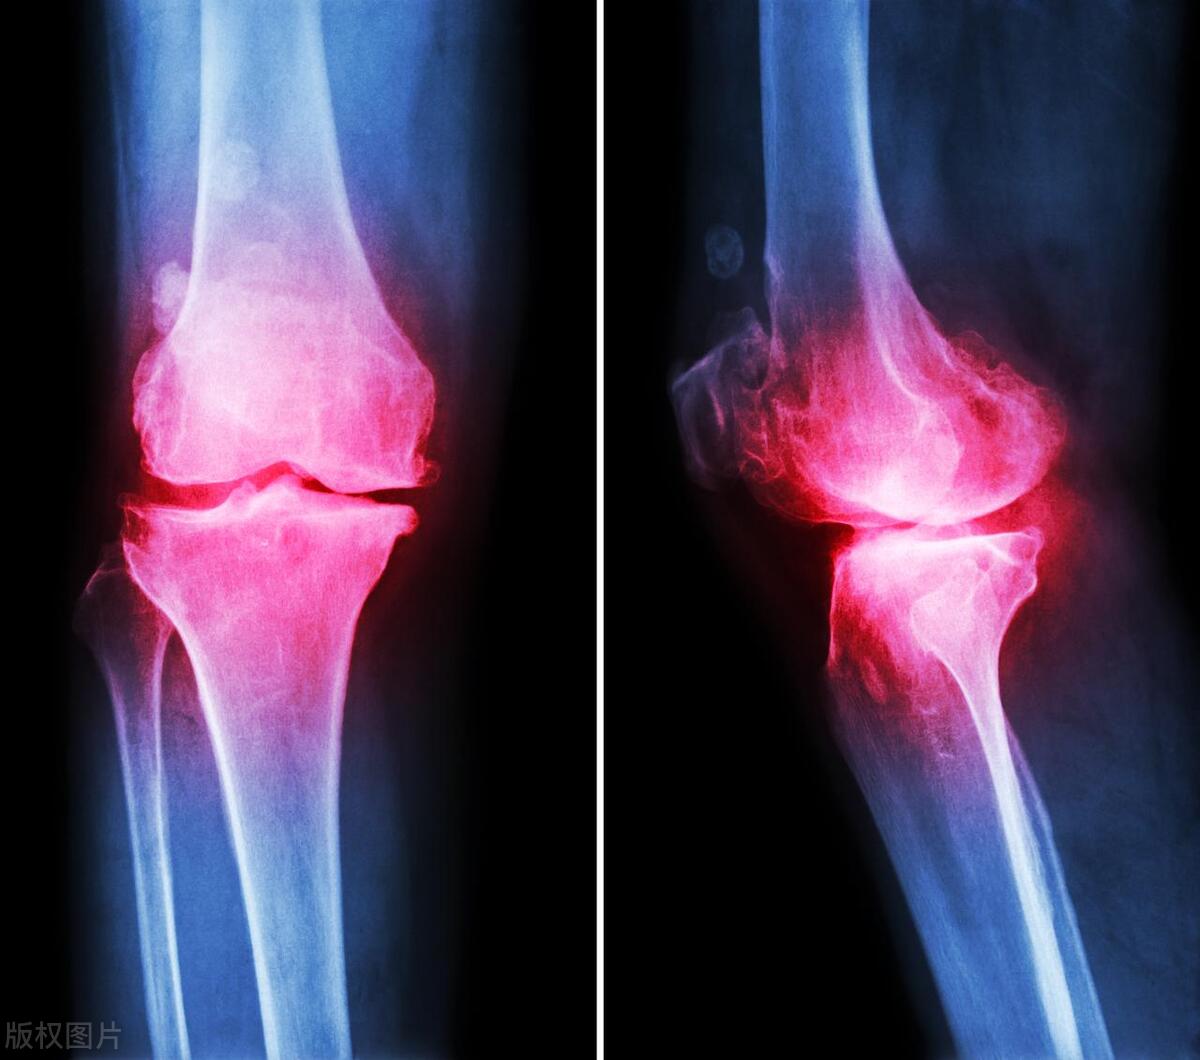

- 膝盖:膝盖是人体最大的关节之一,也是最容易受到压力的关节之一。膝盖骨刺通常发生在膝盖前缘,可能会导致疼痛和不适。

- X射线检查:X射线检查是最常用的检查方法,能够显示骨刺的形状和大小。